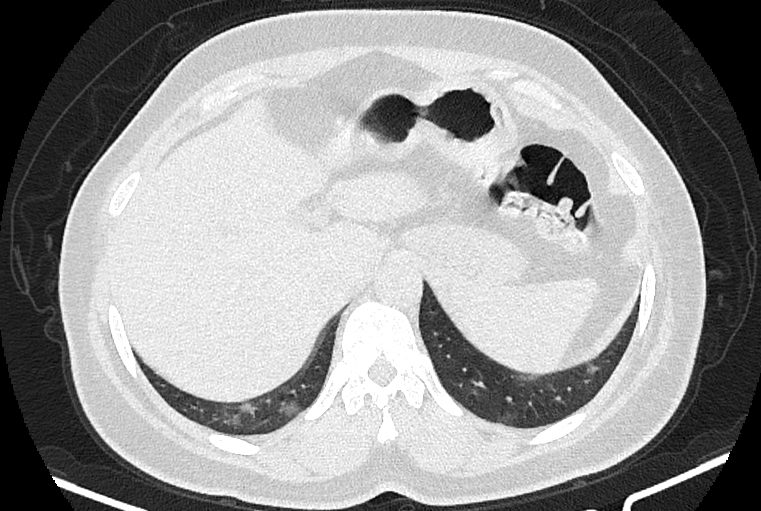

در HRCT از ريه ها(اسپيرال ، مولتي ديتکتور 16، مقاطع اگزيال با ضخامت 1mm بدون فاصله ) ، بدون كنتراست تزريقي :

-کلسیفیکاسیون دیواره آئورت و عروق کرونر ، تغییرات DJD در ستون فقرات ونشانه های CABG مشهود است .

نتیجه : Highly suggestive of COVID-19